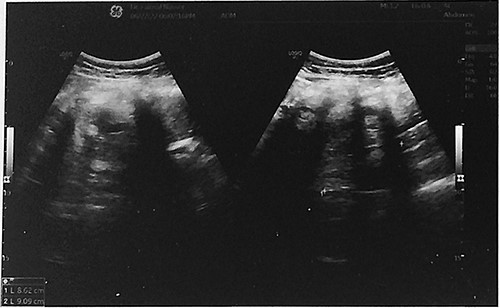

A 48-year-old peri-menopausal female, gravida 4, para 4, all deliveries were by lower segment cesarean sections, presented to the gynecology clinic with the complaint of abdominal pain from the last six months. There was no known history of tumors, particularly gynecological malignancies, in her family. The patient smoked eight cigarettes per day. Routine laboratory tests were within normal limits. Tumor marker CA 125 was 24.4 U/mL (normal range of 0–35 U/mL). Physical examination revealed a palpable abdominal mass with pain in the right iliac fossa. Abdominal ultrasound showed a large, solid cystic mass measuring 8.6 cm × 9.1 cm in size in the right adnexal region (Fig. 1). No abnormal findings were observed in the left ovary. The patient underwent a subtotal abdominal hysterectomy with bilateral salpingo-oophorectomy. The specimen was sent for histopathological evaluation. A gross examination of the right adnexal mass revealed a large cystic teratoma measuring 9.5 cm × 9 cm × 7.5 cm and weighing 307.5 g, filled with hair shafts, greasy brown material, and teeth. The capsule was smooth and intact. Furthermore, a well-defined nodule, measuring 4 cm × 3 cm × 2 cm, was adherent to the teratoma (Fig. 2A). On cross-section, the nodule cut surface was tan with a glairy meaty appearance, and multiple small cysts containing yellow gelatinous material were seen (Fig. 2B). The macroscopic examination of the left ovary specimen showed a small, solid yellow nodular lesion, about 1 cm in maximum dimension, with clear borders (Fig. 2C). The microscopic examination of the teratoma showed a wall lined by stratified squamous epithelium with mature skin appendages (hair follicles and sebaceous glands) (Fig. 3A). Hematoxylin- and eosin-stained sections of the nodule revealed remnants of the ovarian cortex with residual thyroid tissue (Fig. 3B). Well-developed papillae with epithelium composed of cuboidal cells were observed (Fig. 3C). The nuclei have an ovoid, crowded with ground glass (‘Orphan Annie’ eye) appearance. Pseudo-inclusions and nuclear grooves were also present (Fig. 3D). Histological evaluation of the small nodule in the left ovary showed nests and islands of polygonal cells with abundant eosinophilic granular cytoplasm and small, rounded, centrally placed nuclei, surrounded by ovarian stroma (Fig. 4A–C). The mitotic figures were rare. Immunohistochemical stains showed markedly positive staining for inhibin (Fig. 4D). The final diagnosis was papillary thyroid carcinoma arising within a mature cystic ovarian teratoma in the right ovary, coexisting with a stromal luteoma in the left ovary. The malignant tumor was confined to the ovary and has an excellent prognosis. An abdominal and pelvic computed tomography scan was performed, and no regional lymph nodes had metastases. The patient had a stable recovery, and she was discharged a few days after the surgery.

Abdominal ultrasound showed a large solid cystic mass measuring 8.6 cm × 9.1 cm in size in the right adnexal region.